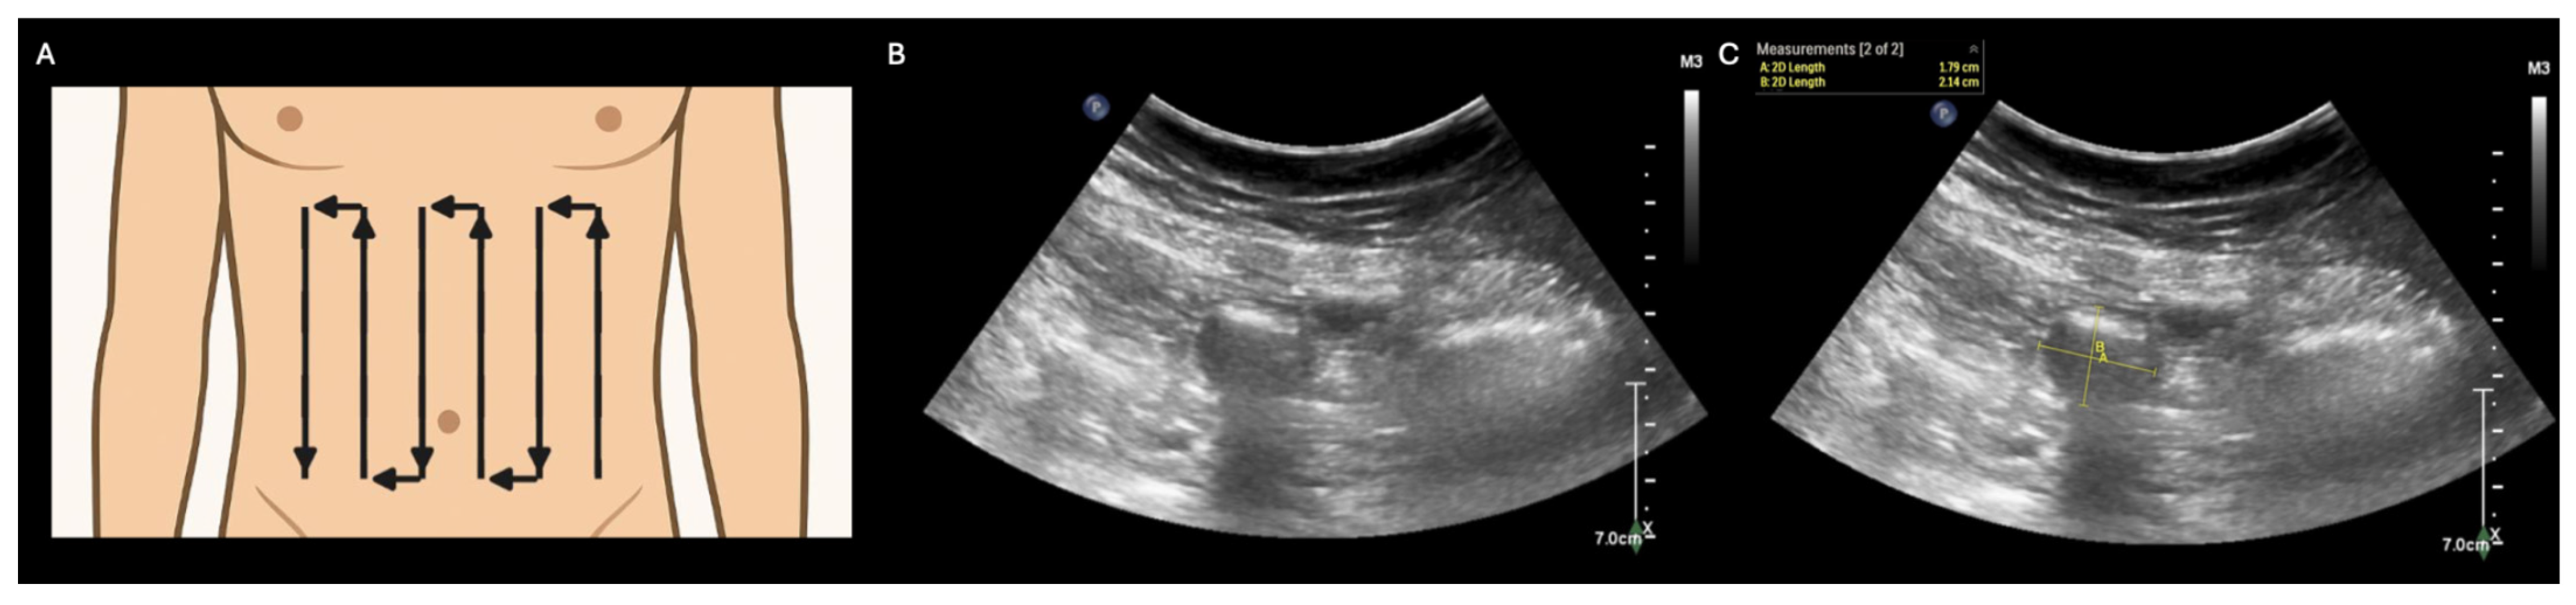

- Abramson, L.; Olive, J.K.; Lefler, B.; Wu, L.; Bowman, A.; Simpson, T.; Vatsaas, C.; Yanamadala, M.; Bronshteyn, Y.S. Point-of-care Ultrasound to Screen for Gastrointestinal Dysfunction: Image Acquisition and Interpretation. J. Vis. Exp. 2025, e68603. [Google Scholar] [CrossRef] [PubMed]